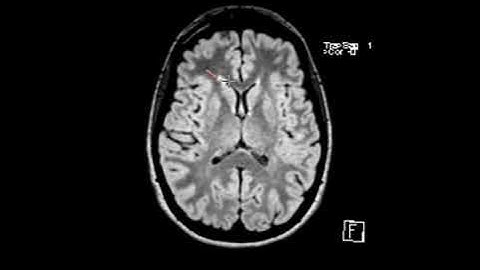

What does MS (multiple sclerosis) look like on brain MRI? Avoid wrongful diagnosis!